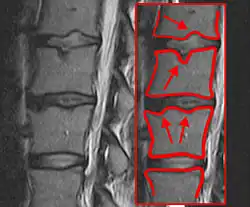

Während des pubertären Wachstumsschubes zwischen dem 11. und dem 15. Lebensjahr bei Mädchen und dem 12. bis 17. Lebensjahr bei Jungen ist die Wirbelsäule besonders anfällig für Fehlentwicklungen. Bei vermehrter Biegebelastung, z. B. durch langes gebeugtes Sitzen (deswegen im Volksmund auch „Schneider-Buckel“ oder „Lehrlings-Buckel“ genannt) und bei gleichzeitig schwacher Rückenmuskulatur (fehlender Gegenzug) werden meist im Bereich der unteren Brustwirbelsäule die Wirbelkörper an den konkavseitigen ventralen Vorderkanten unverhältnismäßig stark belastet, und es kommt zu Schäden an den Knorpel-Knochen-Verbindungen der Deck- und Bodenplatten der Wirbelkörper. Dabei wird die Wachstumszone an den Wirbelkörperkanten beschädigt, wodurch die Wirbelkörper vorne langsamer und keilförmig wachsen. In den zerklüfteten Deck- und Bodenplatten entstehen kleine linsen- bis erbsengroße Kavernen, die mit Bandscheibenmaterial gefüllt sind und als Schmorl-Knorpelknötchen bezeichnet werden. In gravierenden Fällen treten Deckplatteneinbrüche auf. Meistens ist die Distanz der Wirbelkörper zueinander im Verhältnis zur normalen Wirbelsäule stark verringert. Dadurch gerät die Wirbelsäule in eine Fehlstatik. Durch die Keilform mehrerer Wirbelkörper kommt es zur Rundrücken- oder Buckelbildung, d. h. zur verstärkten Kyphosierung der Wirbelsäule. Oft entsteht kompensatorisch im Bereich der Lendenwirbelsäule ein verstärktes Hohlkreuz (Hyperlordose) mit Bildung von Tonnenwirbeln (Erhöhung der Wirbelkörper). Ebenfalls kann es zur Lyse in den Wirbelbögen mit konsekutivem Wirbelgleiten kommen.